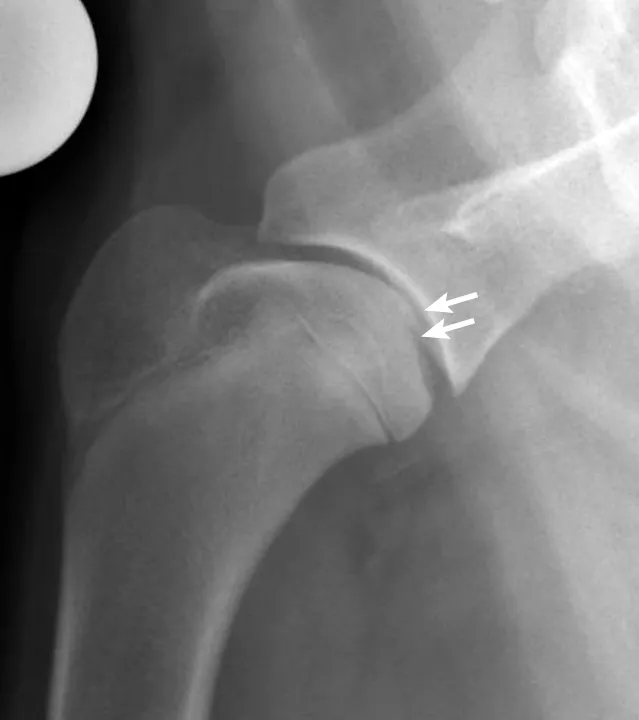

兽医英语学习中心翻译:祁海丽;校对:石慧19 A 6-week-old Boston terrier puppy presents for vaccination. The o...